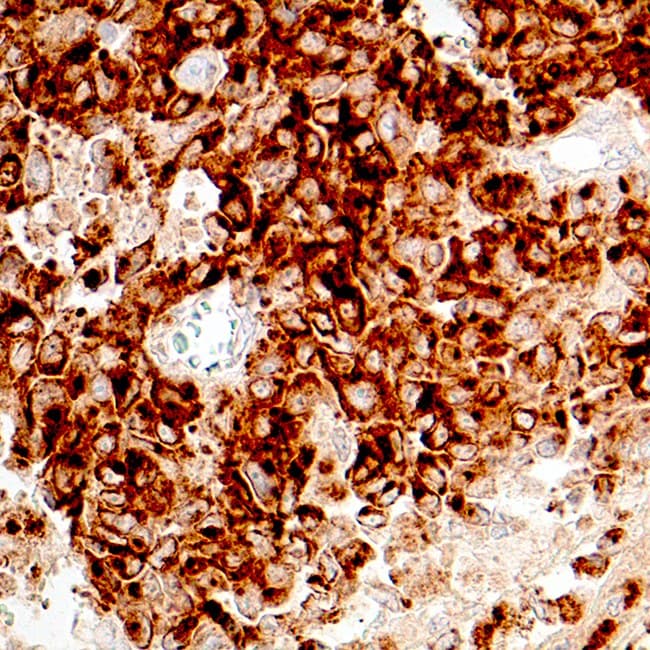

Melanoma section